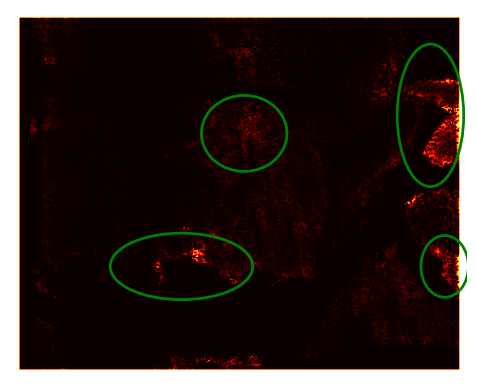

Uncertainty: As the network performs classification, it is easy to acquire the confidence in the predictions (Cao et al. 2018); the closer the Sigmoid output is to 0.5 the less confident the network is. An empirical assessment of the correlation between the disparity error and network confidence was made. It was concluded that there was a correlation between confidence and accuracy. An example of this is shown in Fig. 5. The ellipses highlight the same areas in each image. These results show a correlation between areas of high uncertainty and areas of low accuracy. Fig. 6 displays a histogram plot of the uncertainty and error in the above example. Each histogram bin represents the number of occurrences for each combination of uncertainty and disparity error. A positive correlation is seen between the disparity error and the uncertainty. This is numerical evidence of the correlation observed in Fig. 5. Analysing confidence is critical for healthcare application and the adoption of deep learning methods in clinical practice. This is an advantage for using structured light reconstruction, over disparity estimation, as this is naturally a classification task (where the classification is the final output).

Refer to caption

(a) Disparity error.

(b) Left uncertainty.

(c) Right uncertainty.

Figure 5: Disparity accuracy and uncertainty correlation. The brighter the pixel, the greater the uncertainty and the less accurate. The ellipses are drawn over the same pixels in all three images. Correlating high energy is observed in the areas within the ellipses.